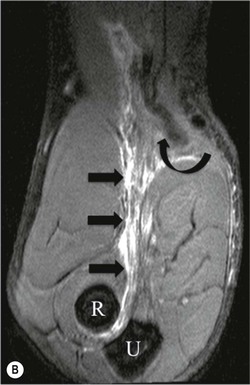

The distal biceps tendon inserts on the tuberosity of the proximal radius. It does not have a tendon sheath, but surrounding connective tissue is known as a paratenon. It is surrounded near the insertion by the bicipitoradial bursa. Distal biceps tears are often clinically unrecognised, but may be amenable to surgery if diagnosed early. In the early stages the tendon is thickened and there may be an effusion in the bicipitoradial bursa (Fig. 46-18). In complete rupture the tendon retracts proximally. MRI and US may be used to confirm the diagnosis and locate the tendon end (Figs. 46-19 and 46-20).